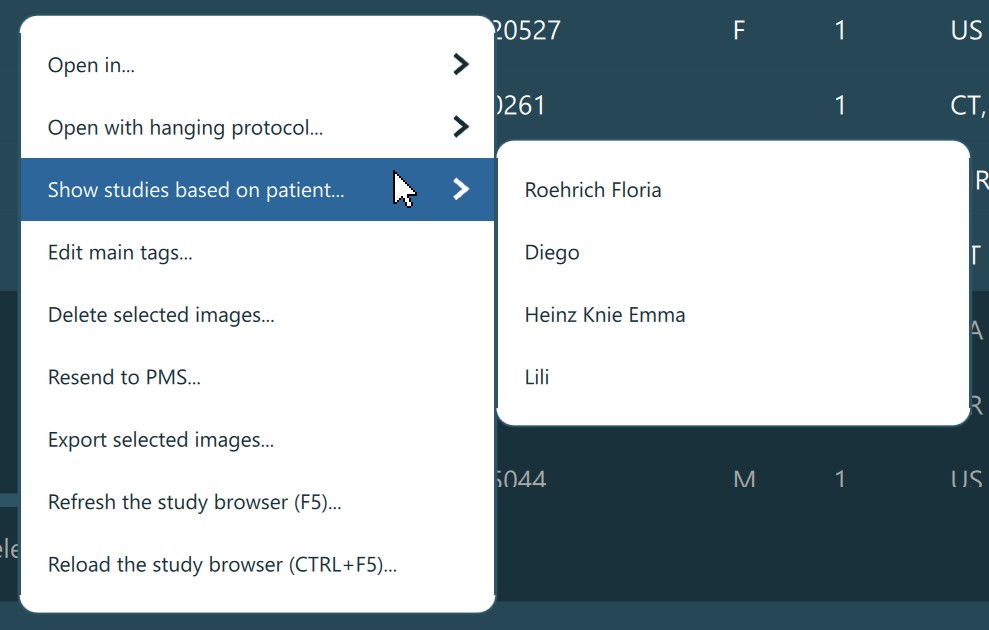

The full database search can also be performed from the Study Browser context menu by choosing the Show studies based on patient... option, and picking the appropriate patient from the ones already selected. If the chosen patient has a valid

patient ID, then the database is queried based on the Patient ID advanced filter. Otherwise, the database will be queried by the Patient name and Owner name advanced filters. The value of the filters is based on the information from the chosen patient.

Patient Mode¶

Patient Mode enabled and toggled on. When the patiend mode is active, the studies in the Study List are grouped into patients, where multiple studies can be related to one patient. To only display studies in the Study List, toggle the patient mode off.Patient Mode option in the settings, which means that the Study List will always be represented with studies only.Refresh Study Browser¶

VisioVIEW offers users the ability to refresh and/or reload the Study Browser content. To simply refresh the browser and fetch only the latest changes, press the Refresh icon in the Study Browser toolbar. To perform a complete reload of the entire Study Browser, hold the CTRL key and press the Refresh icon.

The VisioVIEW Study Browser can also be refreshed by using the F5 keyboard shortcut, or reloaded by using the CTRL + F5 keyboard shortcut. Additionally, the same actions can also be performed from the Study Browser context menu.